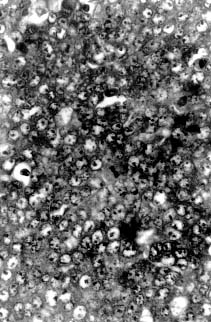

Fig. 1. Large areas of necrosis scattered throughout the tumor forming lobules surrounded by well-defined fibrous strands. 62.5 x, H&E.   Fig. 2. Mitotic figures observed at high power field. 500 x H&E.

Microscopically, the mass was composed of closely packed ribbons and nests of large round to polygonal cells with low amounts of basophilic cytoplasm and large round nuclei with prominent nucleoli divided into demarcated lobules by delicate septa of fibrous tissue. Large areas of necrosis werescattered throughout the mass forming lobules surrounded by well-defined fibrous strands (Fig. 2). The morphology of the tumor cells was consistent with a seminoma. In addition, clusters of small round to oval eosinophilic cells with condensed round nuclei were observed occasionally in the middle of some lobules. A minimum amount of hemorrhage was also observed.